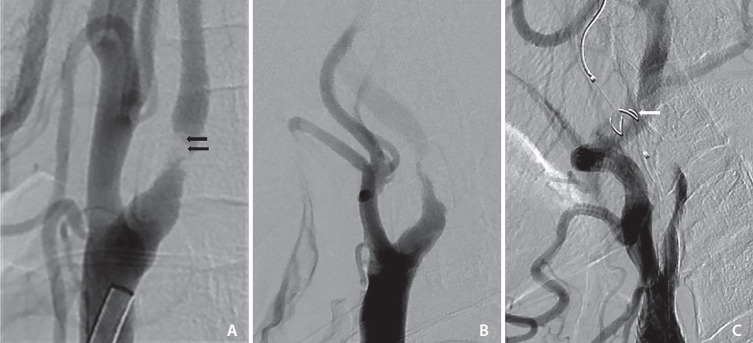

目的:颈动脉斑块的血管壁成像(VWI)能更好地检测不稳定的颈动脉斑块,如斑块内出血(IPH)、富脂坏死核心(LRNC)和薄/破裂的纤维帽。然而,颈动脉支架置入术(CAS)前使用 VWI 的作用尚不明确。因此,本研究旨在确定 CAS 前血管造影和颈动脉 VWI 对无症状颈动脉狭窄的发现,并评估与 CAS 术后临床事件相关的影像学发现:这项回顾性研究纳入了173例连续接受颈动脉VWI、CAS和CAS术后弥散加权成像(DWI)的患者。对颈动脉血管造影(VWI)发现的不稳定斑块和血管造影发现的不稳定斑块进行了分析。我们还分析了CAS术后30天内的临床事件、任何中风、心肌梗死(MI)和死亡的发生率:在173名患者中,101人(58.4%)有初始缺血症状,DWI检查结果呈阳性。有症状的 IPH 患者明显多于无 IPH 患者(62.4% 对 45.8%,P=0.031)。无症状组中狭窄程度、狭窄病变血栓、颈内动脉血流延迟和滤过性血栓阻断血流的发生率明显更高。有 20 名患者(11.6%)在手术后发生了中风、临床症状和/或心肌梗死等临床事件。结论:高脂血症和血管造影显示的腔内血栓是影响CAS术后事件的重要因素:结论:血管造影发现的腔内血栓是影响 CAS 术后临床事件的重要因素。

Results: Of 173 patients, 101 (58.4%) had initial ischemic symptoms and positive findings on DWI. Symptomatic patients were significantly higher in patients with IPH than in patients without IPH (62.4% vs. 45.8%, P=0.031). Degree of stenosis, thrombus of the stenotic lesion, flow delay of internal carotid artery, and flow arrest by filter thrombus had significantly higher prevalence in the symptomatic group. Twenty patients (11.6%) had post-procedural clinical events such as any stroke, clinical symptoms, and/or MI. Hyperlipidemia and intraluminal thrombus on angiography were identified as significant factors influencing post-procedural events after CAS.

Conclusion: An intraluminal thrombus on angiography was identified as a significant factor influencing post-procedural clinical events after CAS.